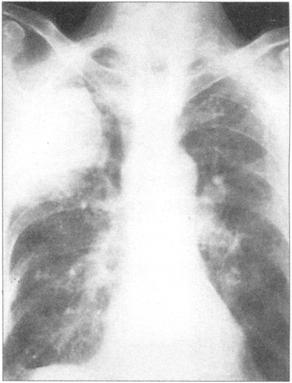

①周围性发绀及周围静脉扩张是由COPD引起的CO2潴留的主要特征(图76)。②脊柱侧后凸常预示患者有某种呼吸系统疾病的倾向(图77)。③结核的X线表现(图78)。④肺尖部结核所致的纤维化多引起上胸部变平(图79),由于脊柱常受累,故多有成角。⑤支气管肺癌(图80)。⑥大叶肺炎患者常伴发单纯疱疹病毒感染(图81、图82)。⑦如肺组织萎陷(如气胸),则胸片上无法看到肺纹理(图83)。

图83 右侧气胸伴肺纹理完全缺失